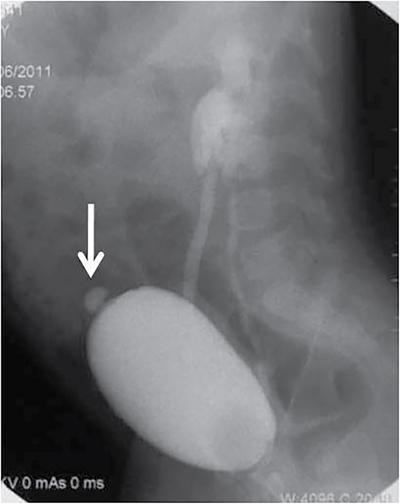

Anmol Bhatia, Kushaljit Singh Sodhi, Akshay Kumar Saxena Congenital as well as acquired anomalies of the bladder and urethra are a significant cause of morbidity in children. Various radiological investigations for imaging bladder and urethra include ultrasonography (US), voiding cystourethrography (VCUG) and intravenous urography (IVU), computed tomography (CT), magnetic resonance imaging (MRI) and contrast-enhanced voiding urosonography. In this chapter, we will discuss and illustrate a wide spectrum of congenital and acquired anomalies of bladder and urethral in children. Foetal allantoic stalk is the connection between the bladder dome and the umbilicus during the embryogenesis. Normally, it gets involuted by the second month of gestation. Depending on the degree of the persistence of this foetal allantoic stalk results in varying types of urachal remnants. The clinical presentation depends on the type of urachal remnant: Fluoroscopy is the best imaging modality for documenting the patency of urachus. However, there may be an underestimation of the exact length of the urachal remnant as inflammation occurring along the tract may block its lumen. CT and MRI are usually not needed for the detection of urachal remnants. However, urachal remnants are usually detected incidentally on CT scan done for other indications. Cystic or solid elongated tubular structure may be seen extending from bladder dome to umbilicus. A focal cystic lesion (Fig. 10.11.3) may be seen in the midline anywhere from bladder dome to umbilicus. In case the urachal remnant present with the symptoms, resection of the entire tract is warranted. Bladder diverticulum are localized outpouching from the bladder wall. They can be single or multiple of varying sizes. A male predominance is seen in comparison to females. It has been traditionally classified into four types: They can be incidentally detected or present with complications including recurrent UTI, urinary retention, incontinence, stone formation, VUR and bladder or ureteric obstruction. Bladder diverticulum should be differentiated from ‘bladder-ears’ in newborn male which is bilateral protrusion of bladder wall into inguinal ring. These are transient and disappear with growth. Appearance of diverticulum depends on cause, location, size and presence of complication features. VCUG under fluoroscopy is most efficient method to demonstrate diverticulum. Fluoroscopic monitoring during all phases including voiding and immediate postvoiding phase is important along with oblique and lateral views. Contained contrast-filled outpouching is seen which may be visible only during voiding phase when urine is forced into diverticulum during bladder contraction. Associated VUR is present in 50% of cases. Round or oval anechoic structure arising in communication with the bladder is seen. Well-defined homogenous structure with fluid attenuation/signal intensity arising from bladder wall (Fig. 10.11.6). Secondary complications like stone formation or rupture can be seen. Surgical removal using intravesical, extravesical or combined approach may be performed along with meticulous repair of bladder wall. Urinary bladder neoplasms are not commonly encountered in children. The majority of bladder neoplasms in children are of mesenchymal origin and overall rhabdomyosarcoma is the most common malignancy (Table 10.11.1). They can be incidentally detected or present with urological symptoms including dysuria, haematuria, incontinence and lower abdominal pain. It can manifest as filling defect in MCU studies done for other indications. Ultrasound is usually the first line investigation with cross-sectional imaging being performed in suspected cases for accurate characterization, localization, disease extent and complication. Histopathological analysis is often needed for final diagnosis. The differential diagnosis of bladder masses includes masses arising from adjacent pelvic structures, variants like ureterocoele or urachal remanent, mass forming cystitis (eosinophilic cystitis, BK virus–associated cystitis), haematoma, calculi or iatrogenic materials (e.g. Deflux used in VUR surgeries). Rhabdomyosarcoma Leiomyoma Neurofibroma IMT Leiomyosarcoma Angiosarcoma Haemangioma Urothelial carcinoma PUNLMP: urothelial papilloma Fibroepithelial polyp Paraganglioma Nephrogenic adenoma PUNLMP, papillary urothelial neoplasm of low malignant potential. Rhabdomyosarcomas are the most common urinary bladder neoplasms in first two decades of life presenting typically at ages 2–6 years and 15–19 years. Syndromic association with Li–Fraumeni cancer syndrome, NF type 1, MEN 2A has been found; however, majority are sporadic in origin. Histological subtypes include embryonal rhabdomyosarcoma (classical, botryoid and spindle cell variant), alveolar and undifferentiated sarcoma types of which embryonal form accounts for 90% of all cases. Locoregional spread to adjacent organs, muscles, regional lymphnodes is seen with distal metastasis to lung, cortical bones and retroperitoneal lymphnodes. Metastasis is found in approximately 10%–20% of patients at time of initial presentation. Overall survival and outcome depend on patient age and histological subtype with patients between 1–9 years of age and embryonal subtype having a better prognosis. Imaging work-up includes CT or MRI pelvis for local disease characterization and extent, CT chest, bone scintigraphy or FDG-PET for metastasis and staging. They commonly arise from bladder trigone and neck area. Ultrasound: They are typically large, intraluminal, multilobulated masses with well-defined margins and homogenous hypoechoic or hyperechoic echotexture. Foci of necrosis or haemorrhage are often seen. Vascularity on colour Doppler is increased. Hydronephrosis and bladder neck obstruction secondary to mass can be found. CT: Bulky heterogenous low attenuation mass that may invade into periurethral or perivesical tissue (Fig. 10.11.7). Calcification is rare.